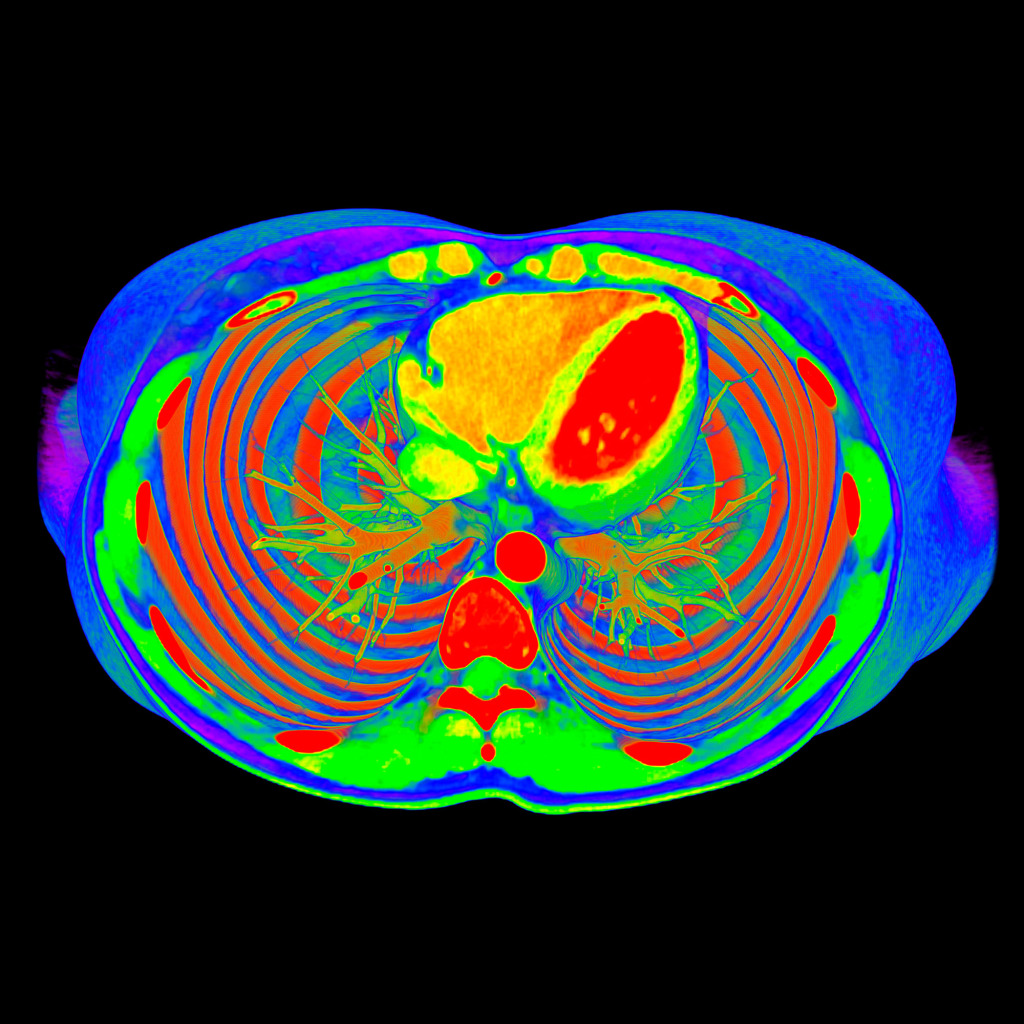

Most of the time, radiologists work with black and white images.

A multi-coloured, bright image is a way to shift the gaze and perceive things differently.

Also, I like to experiment with different photo filters and settings.

The program for processing radiological images (DICOM archives) allows you to create and look at a three-dimensional image from different angles.

If you change the location of the virtual lens, thereby changing the perspective, you can get such images.

How do you decide which colours to use on the images?

The colours choose themselves.

I simply create a table where the radiological density of the material can correspond to any colour.

After combining different shades, I only have to choose what I like the most.

No. Tissues with different densities are best suited to visualisation by CT imaging.

Lungs and heart, bones and muscles or organs injected with a contrast agent reveal the best structure and anatomy.